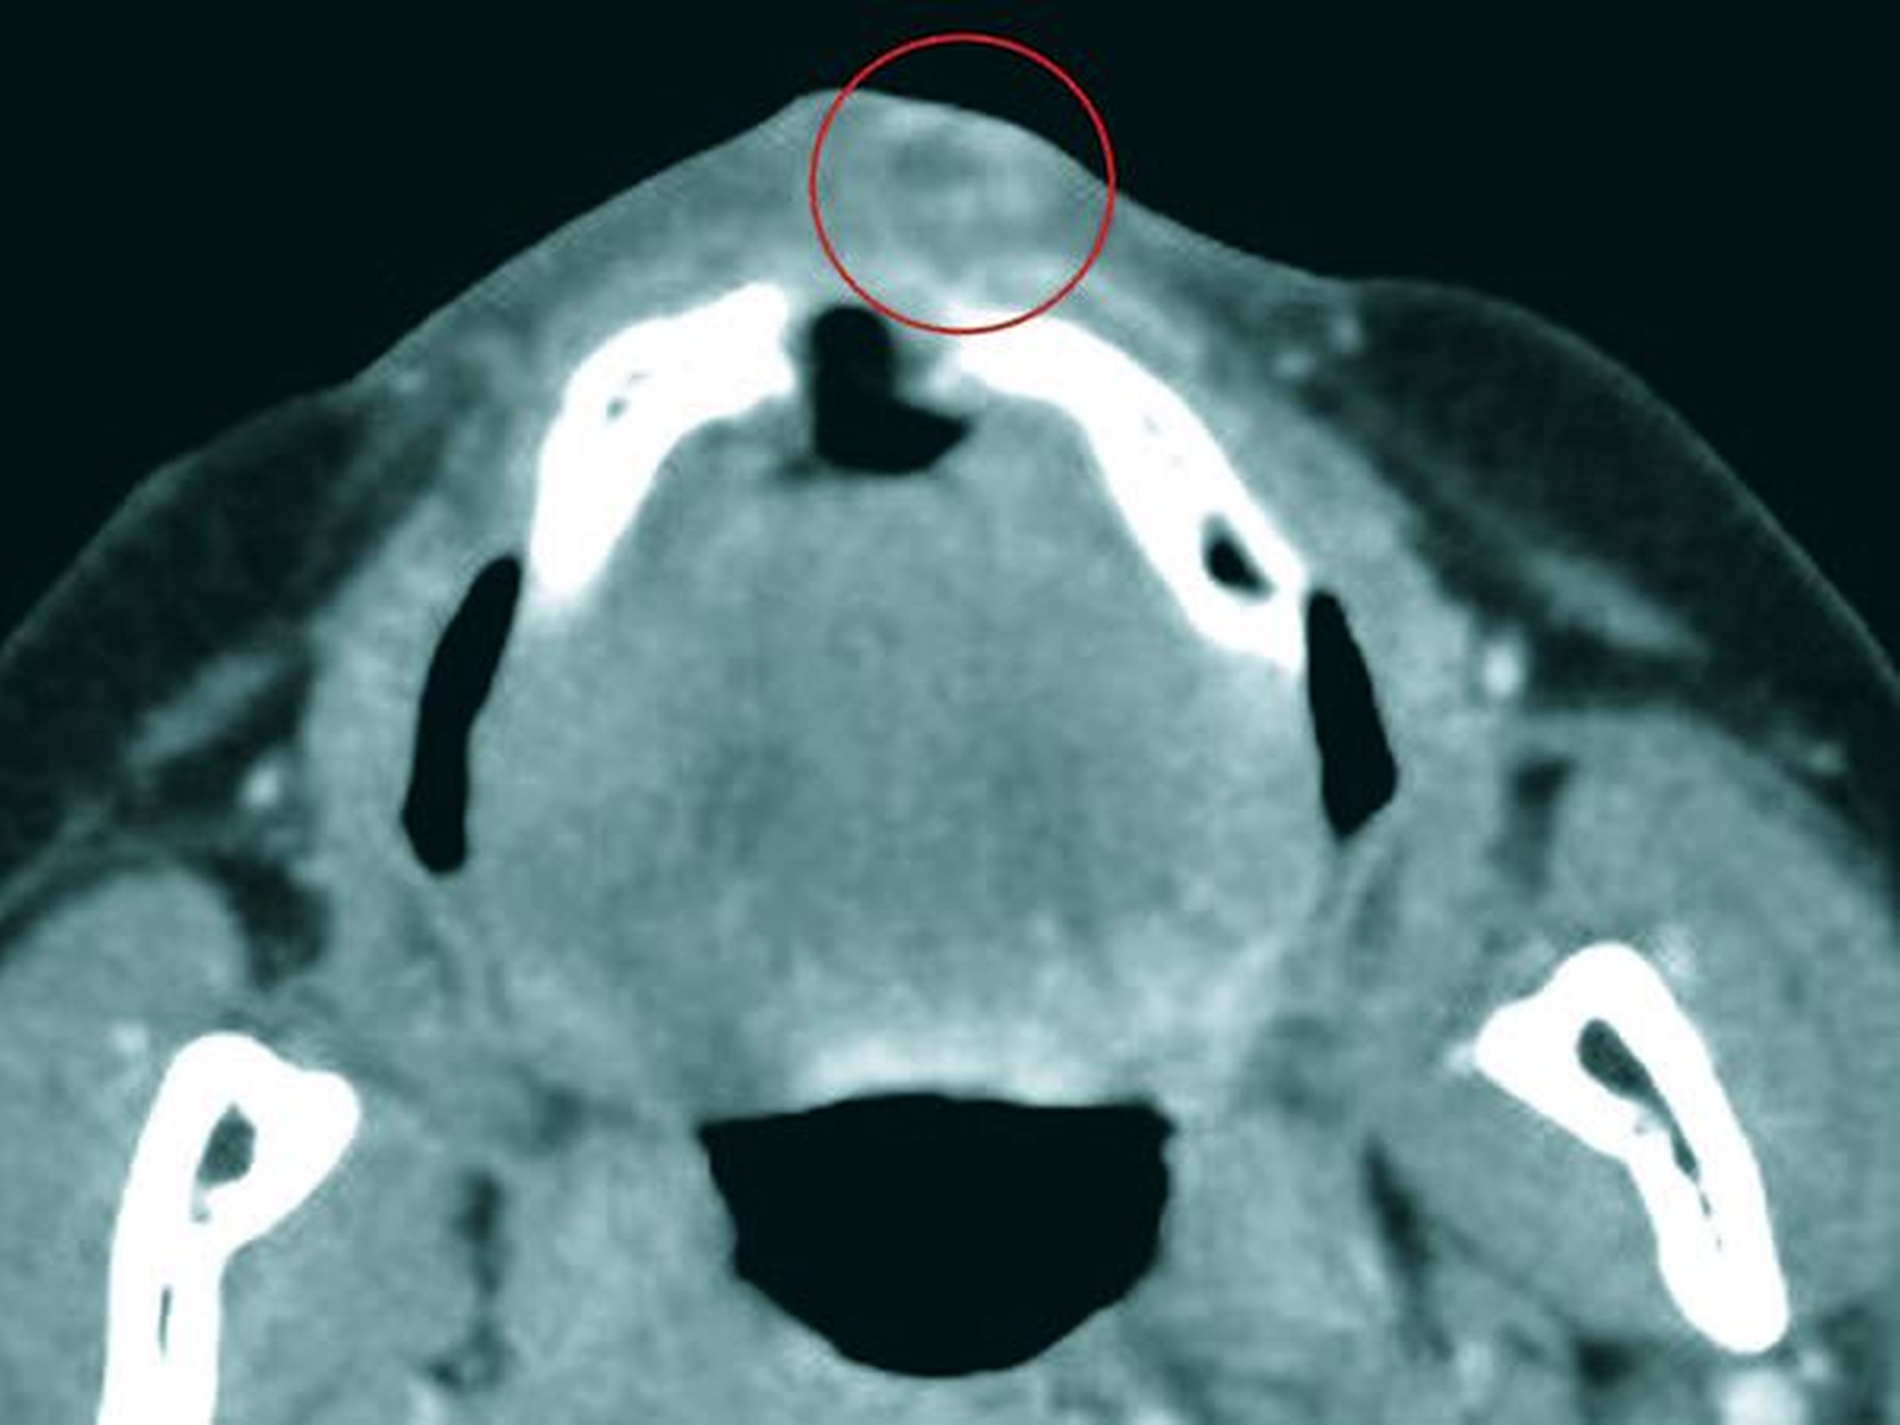

Das anschließende Tumorstaging (Kopf/Hals-CT und Thorax-CT jeweils mit Kontrastmittel, Sono Abdomen, HNO-SpiegelUntersuchung und Ösophago-Gastro-Duodenoskopie) ließ außer dem radiologischen Befund einer 5 mm x 10 mm durchmessenden Kontrastmittel-aufnehmenden Raumforderung im Bereich der Oberlippe links (Abbildung 3) keine weiteren Auffälligkeiten erkennen.